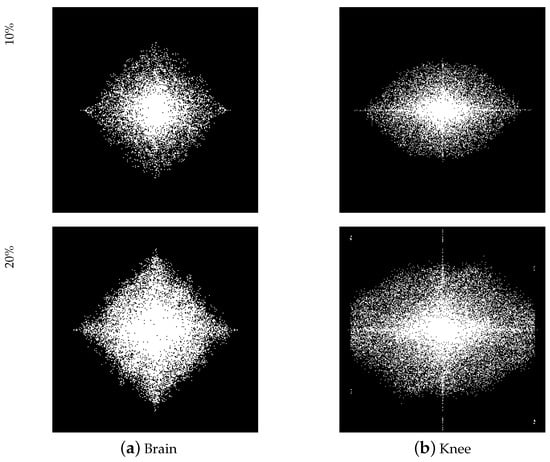

Figure 4 shows a visual comparison between the classical mask and our trained optimized sub-sampling ratio for | | S | | 0 = 10 % and | | S | | 0 = 20 % . It can be seen that the learned 2 D mask exhibits a strong preference for lower frequencies and a denser sampling pattern closer to the origin of K-space, which is also in line with prior knowledge, i.e., the lower frequency part has greater energy.

In addition, Figure 6 compares the differences in the anatomical optimization of the knee and brain joints of our model. We observed that for MR images of the knee, due to the unique asymmetrical features of knee anatomy, give more importance to the lateral frequency direction, with obvious tissue contrasts. Conversely, the masks learned on the Brain dataset appear to be more balanced in all frequency directions. Such data comparison results show the importance of learnable masks, and it is necessary to customize sampling masks of different structures for data with different structures. It is worth noting that the masks learned on the Brain and Knee datasets at 10 % show high intermediate density and low peripheral density. At 20 % , the Knee mask maintains this feature, but the Brain mask has a high density within its data structure, which may indicate that the sampling ratio of 20 % is good enough to restore good results for the Brain dataset but not for the Knee dataset. The experimental results given in Table 2 also illustrate this.

Figure 4. Visual comparison of different masks on the Brain dataset. The CS ratios are set to 10% and 20%. Our learnable masks have a clearer data structure than other masks, and also satisfy the priors of low frequency density and high frequency sparseness.

Figure 6. Visual comparison of learned masks on Brain and Knee datasets with CS ratios of 10% and 20%. The masks learned on the Knee dataset appear to give more importance to the lateral frequency direction, with obvious tissue contrasts, while the masks learned on the Brain dataset appear to be more balanced in all frequency directions.